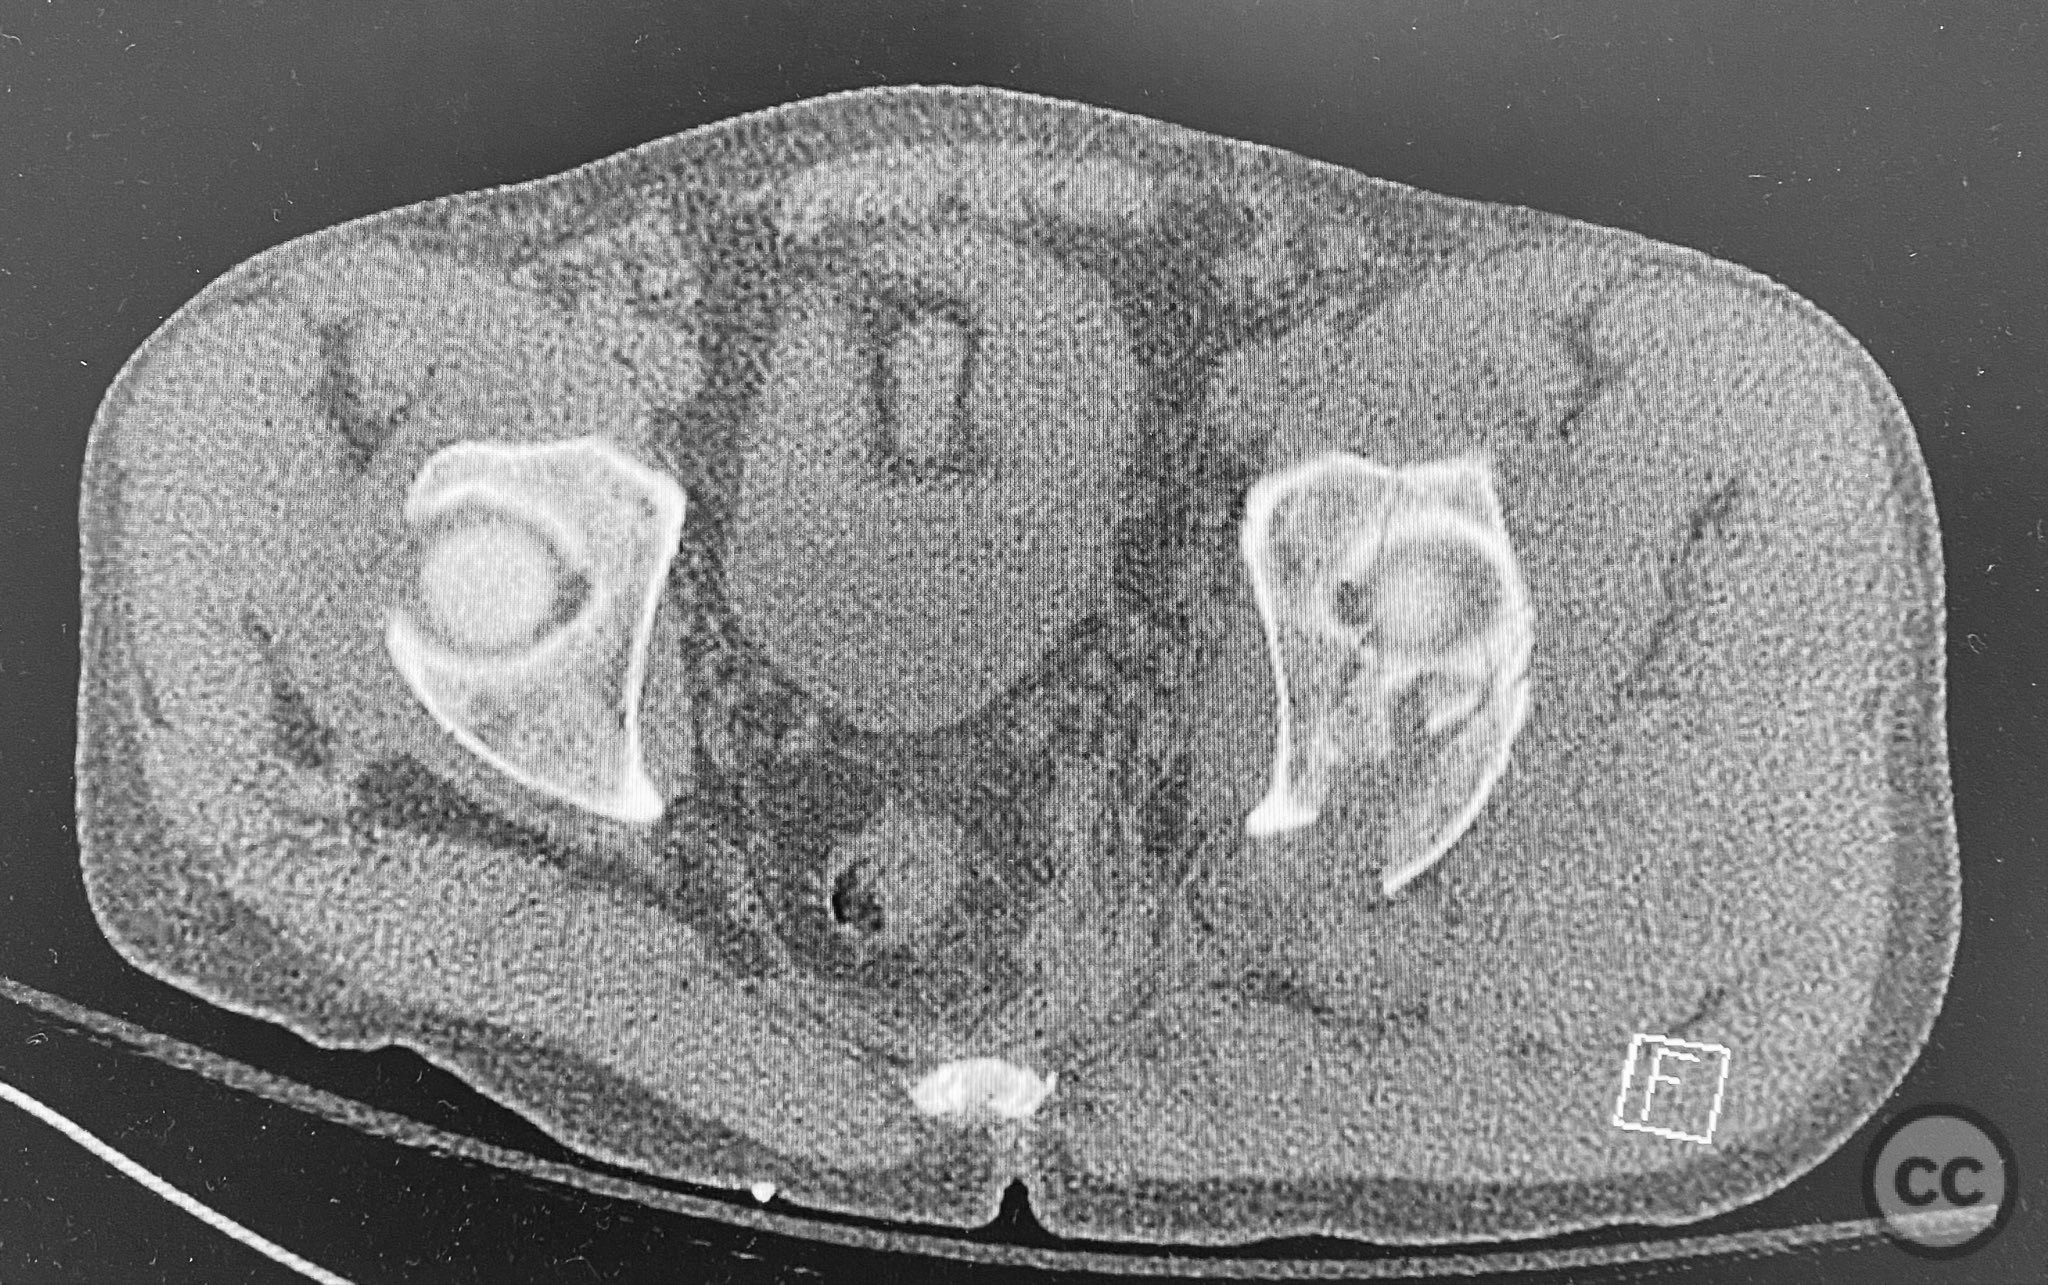

Clinical and radiological findings:  A patient presented with a seemingly non-comminuted, wide, and long posterior wall (PW) acetabular fracture fragment. Axial computed tomography (CT) images demonstrated the thickness of the PW fragment, the articular surface, and multiple areas of subchondral impaction. Preoperative planning identified the size, location, and depth of the impaction zones, as well as an essentially nondisplaced transverse acetabular fracture line, which was not readily apparent on initial imaging. No significant displacement of the transverse component was noted. The AO/OTA classification is 62-B1.3 (posterior wall and transverse acetabular fracture).

Planning remarks:  The preoperative technical plan included a prone Kocher-Langenbeck (KL) approach to access the posterior column and wall. The plan entailed elevation and reduction of impacted articular fragments, bone grafting of subchondral defects, anatomical reduction and provisional fixation of the posterior wall fragment, and definitive fixation with a contoured plate. Intraoperative fluoroscopy was planned to guide additional screw placement through the plate to stabilize both the posterior wall and the transverse fracture line. A supplementary medial plate was planned to augment fixation of both the posterior wall and transverse components.